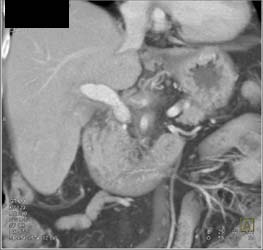

Fibrolamellar Hepatoma With Neovascularity